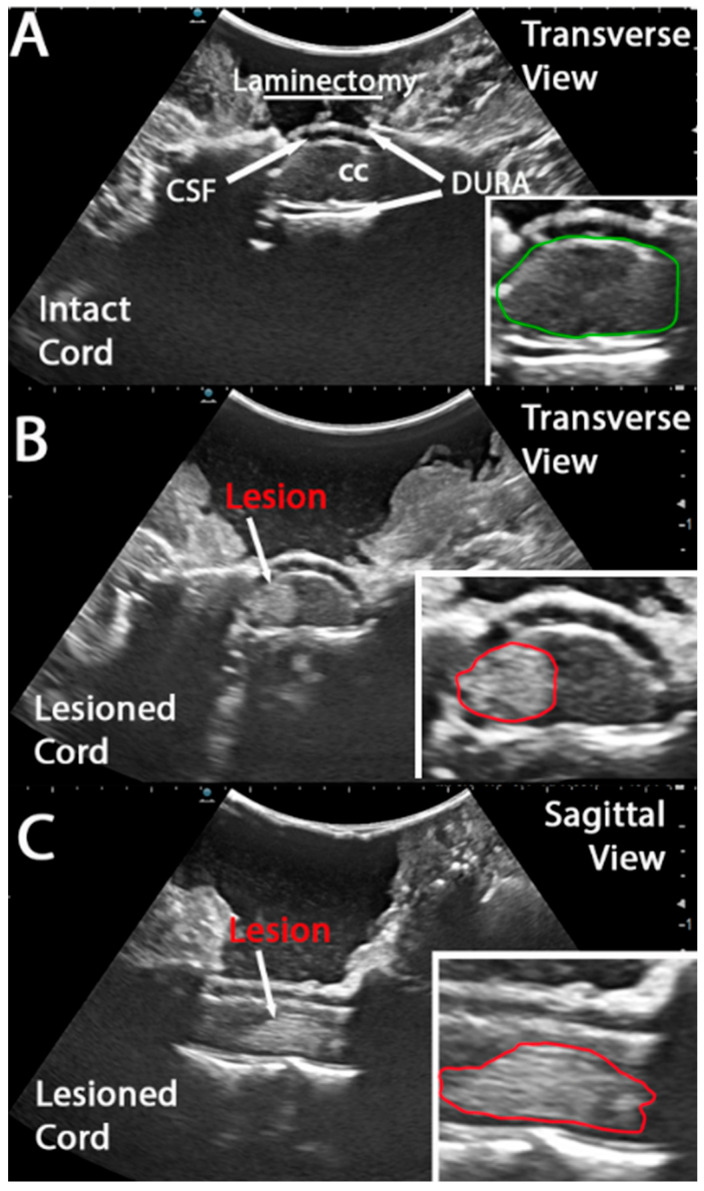

Methods: In this study, we implemented an intra-operative ultrasound (IOU) approach to precisely locate and examine the lesion site at 5 and 10 min post-injury after a cervical hemi-contusion injury in a non-human primate (NHP) model. We assessed acute lesion progression from 5 to 10 min and then compared that to the lesion extent as measured by MRI 3 weeks later.

Conclusions: By enabling high-resolution ultrasound visualization of the hemicontusion lesion in vivo, this approach can provide critical insights into the early progression of SCI. It can help with further refining this preclinical SCI model and provide significant predictive value for the animals' recovery post-injury.